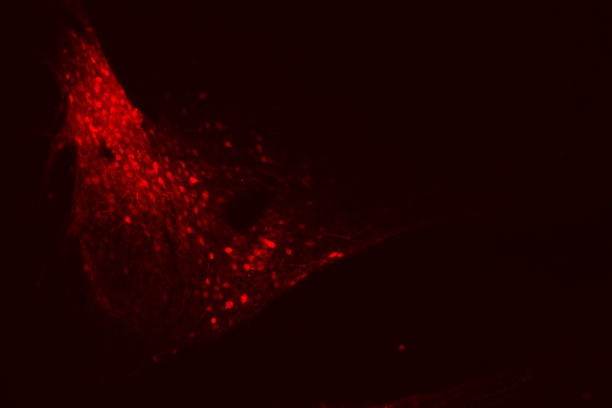

Sudden unexpected death in epilepsy (SUDEP), the enigmatic pathology whereby epileptic patients are found to have died without another cause, is the most frequent cause of death in epilepsy patients. The rare cases of SUDEP in healthcare settings show a sequence where apnea precedes terminal cardiac arrhythmias, implicating death due to respiratory decline. From our work and the work of others, it is clear that the amygdala has an underappreciated role in breathing. Our research aim is to investigate these brain regions through multidisciplinary approach to determine their role in epilepsy, apneas, and SUDEP.